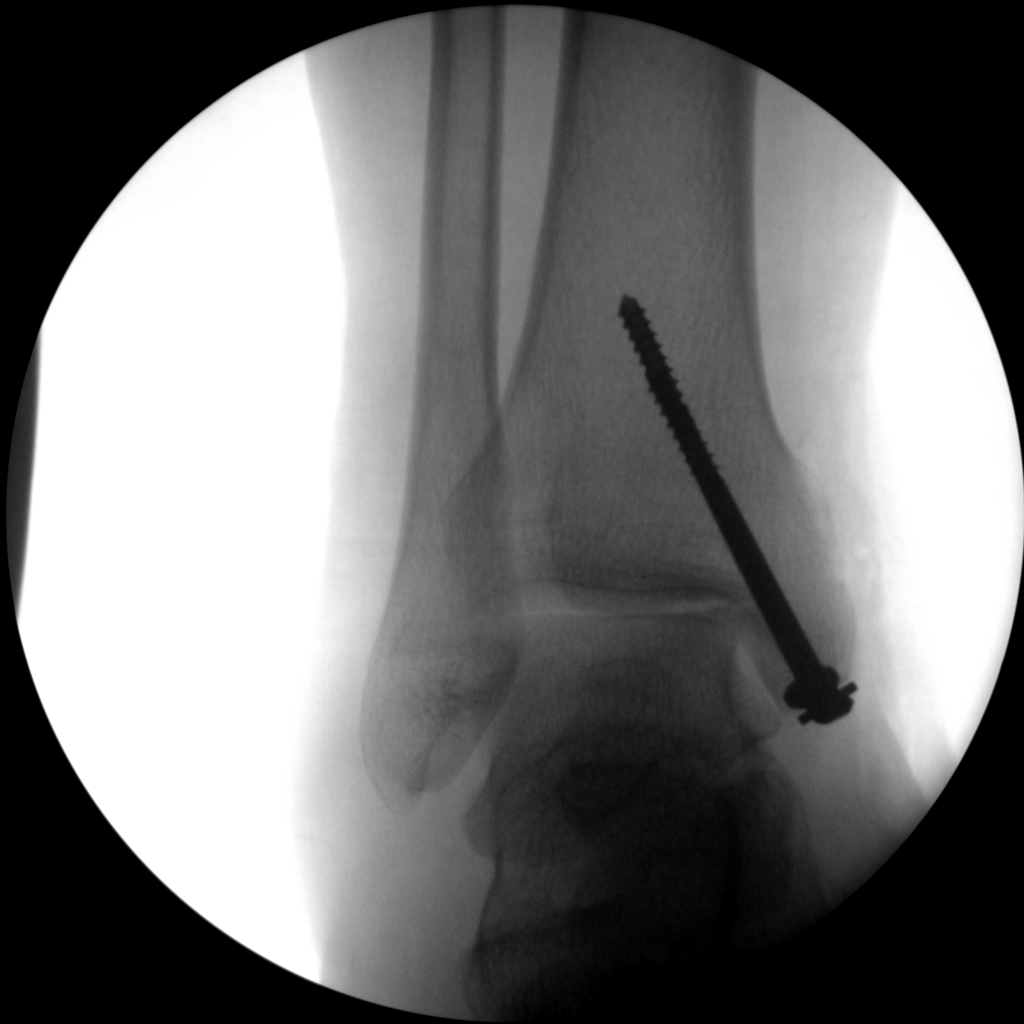

CRIF - Closed reduction internal fixation

ORIF - Open reduction internal fixation

Skan-C is a great C-arm for orthopaedic treatments for several reasons